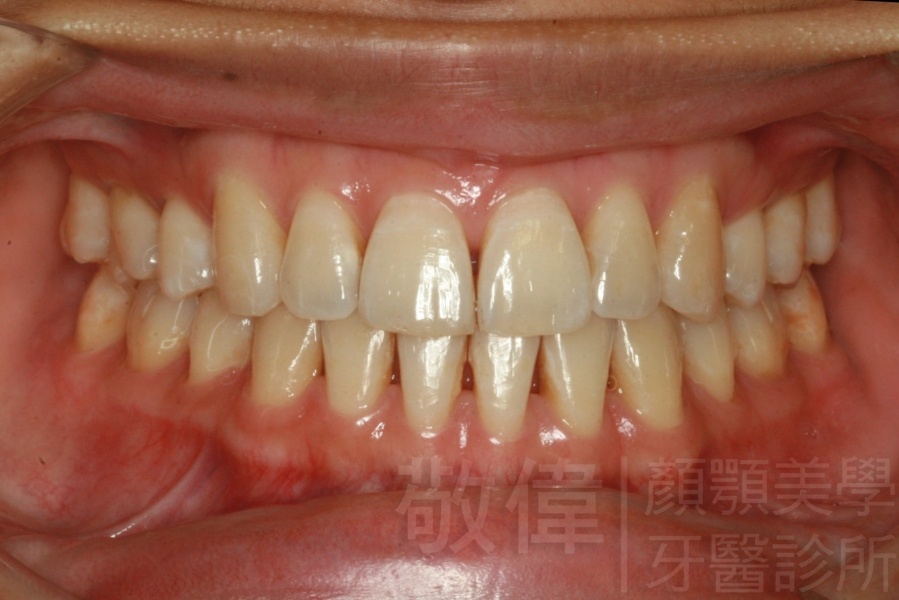

變臉矯正,原來戽斗妹跟大歪臉變成自信正妹

經由本院3D數影X光影像儀分析、與3D齒顎顏矯正技術,再配合口腔顎面正顎專科醫師施以正顎手術治療,雙方共同合作,使患者臉部外觀有很好的改善,大歪變小歪,產生了天南地北的大改變,她的人生也整個變得不一樣。

因為矯正與正顎手術的配合,使「戽斗妹」變成了「陽光正妹」,完全的改變了她的人生,在面對各種場合、與人交際都散發出自信微笑。所以,奉勸家長,如果小朋友有臉顎畸型的問題,應該考慮配合做這種簡單、安全、有效的正顎手術。

「3D齒顎顏矯正」,不止矯正您的牙齒,也會改變您的人生。「治療前」和「治療後」出社會的人生際遇一定會截然不同。